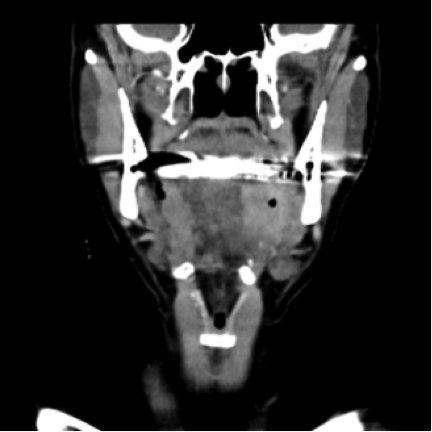

The clinical examination revealed an ulcerated and enlarged left tonsil and left cervical lymphadenopathy levels II and III. A Neck CT Scan with contrast medium revealed a mass on the left tonsil. A Thorax+Abdomen CT Scan with contrast medium revealed no metastasis. We performed a Panendoscopy and the pathologist described it as a squamous cell carcinoma (G2) with p-16 expression.